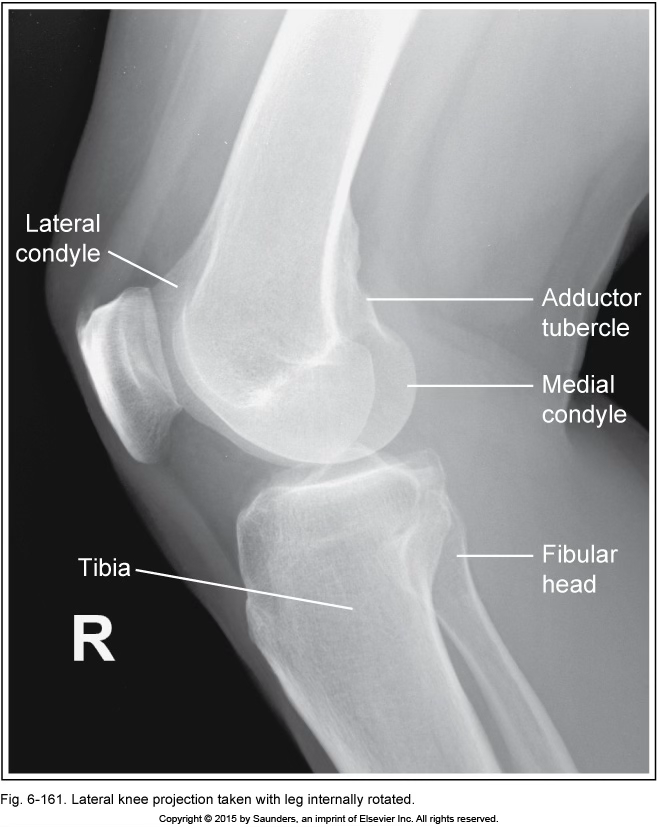

lateral knee

leg internally rotated